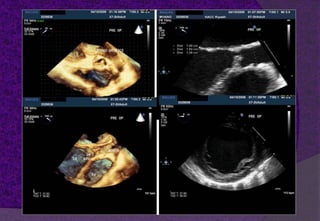

 The Aortic Root, represents the outflow tract

from the left ventricle, provides the

supporting structures for the leaflets of the

aortic valve, and forms the bridge between

the left ventricle and the ascending aorta.

 It extends from the basal attachments of the

leaflets Within the left ventricle to the

sinotubular junction